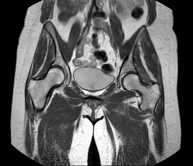

Exploració per a l'estudi de lesions a tendons, músculs i articulacions coxofemorals. Permet identificar de manera precoç l'artrosi de maluc. Resulta molt útil per detectar les bursitis i l'osteopatia dinàmica de pubis, freqüent en esportistes. La durada aproximada és de 20 minuts. No utilitza radiació ionitzant. - RM de Sacroilíaques

Estudi específicament dissenyat per valorar aquestes articulacions i la seva inflamació en els pacients que pateixen espondilitis anquilosant. També resulta d'utilitat en pacients amb traumatismes i possibles fractures del sacre i el còccix. La durada aproximada és de 16 minuts. No utilitza radiació ionitzant. - RM de Glutis